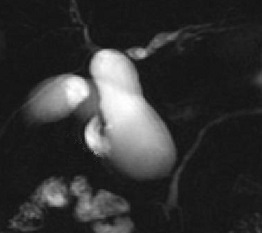

Image radiologique Bili-IRM

d'une kyste choledoque de type Ia recontruit

en 3D . Image de la vesicule biliaire se retrouve

tres nette en position horizontale pres du kyste . |

Dilatation multi kystique

intrahepatique de voie biliaire de type V .(

Maladie de Caroli ). Image radiologique cholangio-IRM

recontruit en 3D de voie biliaire . |